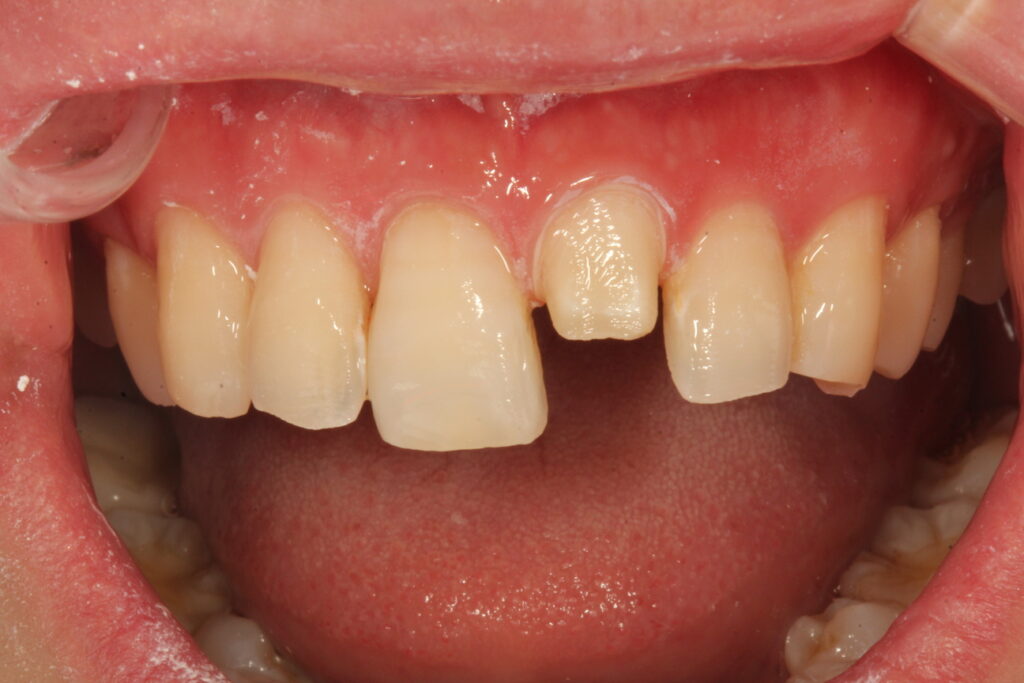

앞니 한 개만 돌출이 되어 웃을 때 신경이 쓰여서 치료받고자 하는 환자였습니다. 이 분은 치아교정이 아닌 단 하루에 치료를 마무리할 수 있는 방법을 선택해서 하루만에 치료를 마무리한 치료전후입니다.

해당 사례를 치료하는 과정입니다. 심하게 돌출되어 있던 앞니를 안으로 넣기 위해 충분한 삭제가 필요했고 그래서 해당 치아는 충분히 삭제 후 크라운으로 치료를 합니다.

돌출이 심한 치아를 주변치아 정도의 위치까지 삭제하게 되면 치아법랑질은 모두 사라지게 됩니다. 그렇기 때문에 법랑질에 강력하게 부착해서 치아와 한몸이 되는 라미네이트 치료를 돌출된 치아에는 할 수 없는 것입니다. 법랑질이 충분하지 않은 부분에 라미네이트로 만들어 앞에만 붙이면 금새 떨어지게 되기 때문입니다.

그래서 한 개의 치아는 예방적 신경치료후 올세라믹크라운으로 치료합니다. 나머지 치아들은 비교적 고른 편이라 라미네이트가 잘 붙게 하기 위한 정도의 다듬기만 해 주거나 삭제를 하지 않습니다.